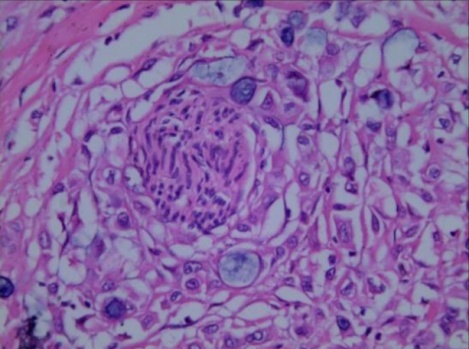

α) Νεκρωτική αγγειίτιδα. Διατοίχωμα φλεγμονή του αγγειακού τοιχώματος, με ή χωρίς ινοειδή νέκρωση. β) Νεκρωτική αγγειίτιδα μεσεντερικής αρτηρίας, με παναρτηριακή νέκρωση και παρουσία ινοειδούς νέκρωσης αγγειακού τοιχώματος. Ευγενική παραχώρηση Dr. V. Penopoulos.